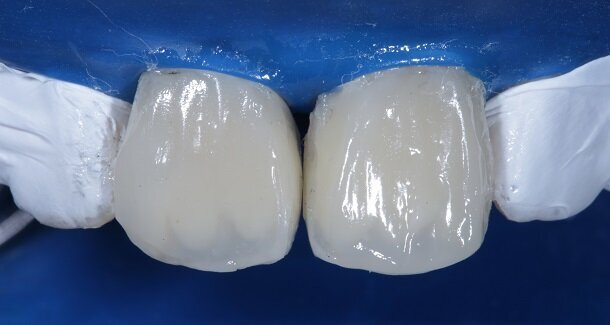

The figures show the clinical work flow involved. In the 1st appointment Oral prophylaxis, oral hygiene instructions were followed by an impression that was sent to the lab for a wax up [Fig 3 and 4]. In the subsequent appointments, Endodontic treatment was followed by Intra and extra coronal office bleaching using the Pola office bleaching kit. After two weeks, the shade stabilised post bleaching. Shade selection, rubber dam isolation and preparation was done on both the teeth to receive Direct composite veneers so as to close the midline diastema as well as correct the fractured teeth and the slight mal-alignment. Controlled Body Thickness (CBT) technique of layering was used with 3M Z350XT shades - Dentin shades A3, A2 and Enamel shades A2, clear translucent [Figures 5 to 11]. This was followed by the Finishing and polishing protocol as described in the figures.

Characterisation begins during Dentin Layering itself. [Fig 9] Shape of the tooth is extremely important. A well-made putty key from a wax-up or a mock-up can help in maintaining shape of the tooth. [Fig 3 and 4]